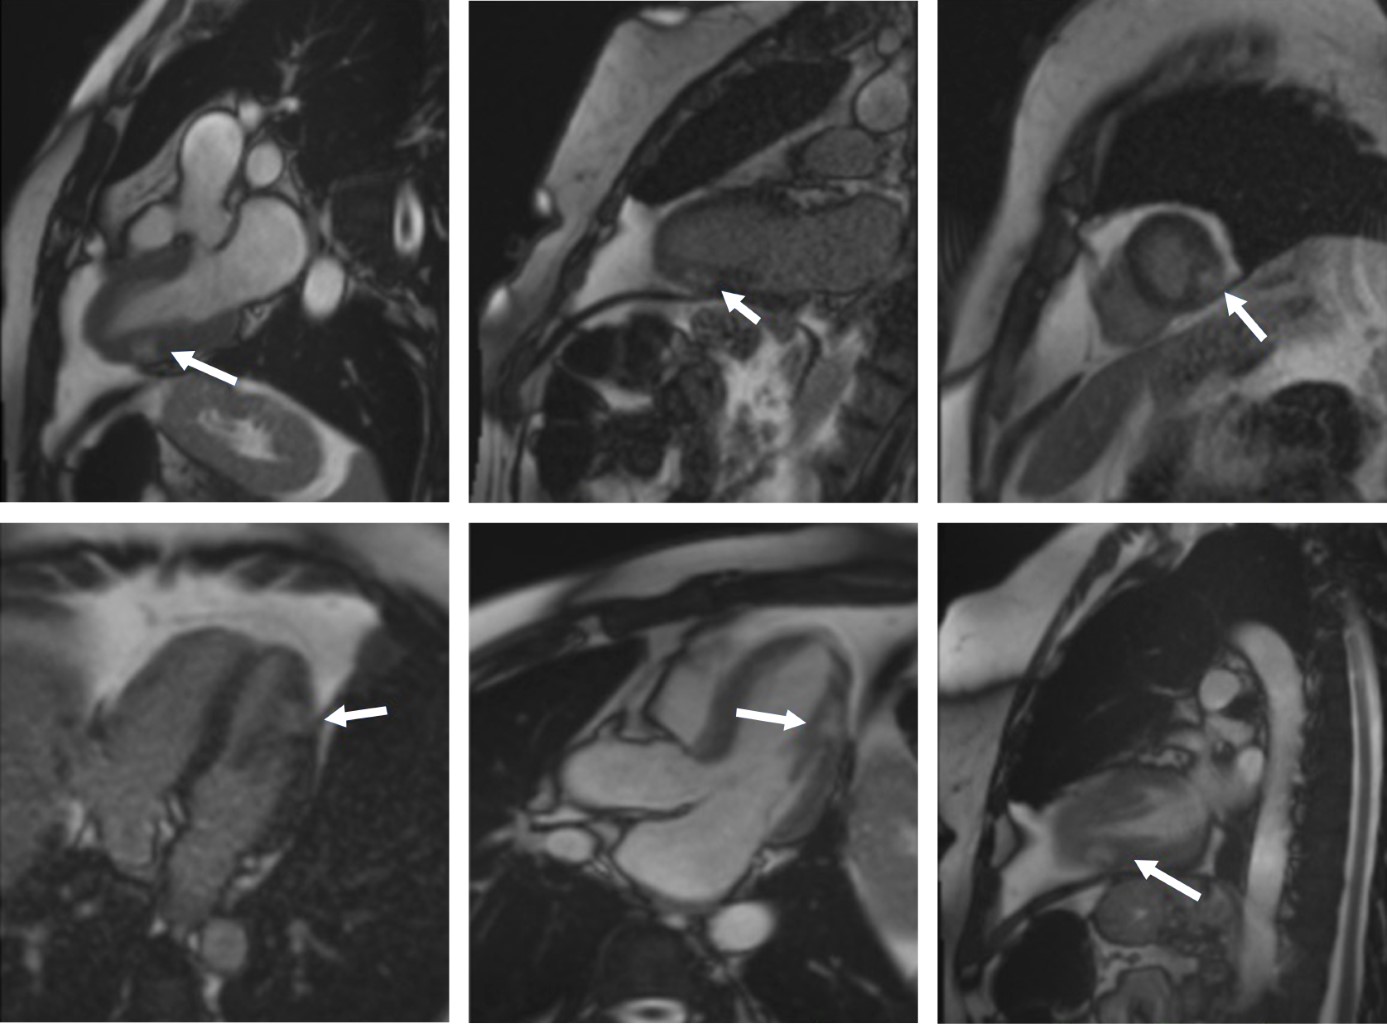

Se presenta el caso de una mujer de 50 años atendida en el Servicio de Urgencias por dolor torácico y elevación de enzimas cardiacas; no tuvo alteraciones electrocardiográficas. Se realizó coronariografía en la que no se encontraron lesiones obstructivas. Un estudio de resonancia magnética cardiaca reportó imagen compatible con miocarditis aguda sin evidencia de isquemia miocárdica. La paciente había recibido una primera dosis de vacuna Pfizer-BioNTech dos días antes de la aparición de los síntomas. En la mayoría de los casos de miocarditis, el diagnóstico etiológico se encuentra indeterminado y sus manifestaciones clínicas tienen un amplio espectro. En los últimos meses, se ha establecido la asociación probable entre casos de miocarditis con vacunas COVID-19 mRNA. El uso de vacunas COVID-19 mRNA ha demostrado el beneficio significativo en la reducción de morbilidad y mortalidad relacionadas a la infección por el virus SARS-COV-2. Este puede ser un proceso transitorio que no representa una contraindicación para la aplicación de la vacuna.

Figura 2